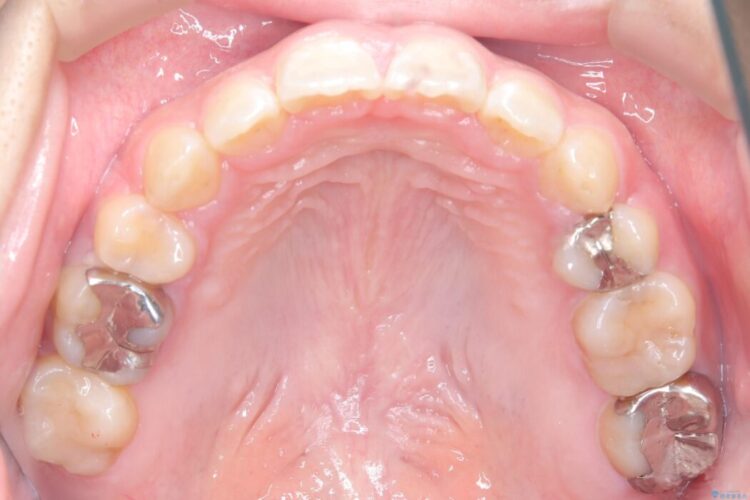

精密検査の結果、前歯を大きく後退させるスペースが必要と診断しました。

「前歯を下げたい」という患者様の強いご希望に応えるため、上下左右の第一小臼歯を抜歯。そのスペースを利用し前歯を奥へ移動させる治療計画を立案しました。

今回の矯正治療では、前歯を大きく後退させるスペースを確保するため、計画通り上下左右の第一小臼歯を抜歯しました。

装置には、上顎には目立たない裏側矯正(舌側矯正)を、下顎には透明な審美ブラケットを使用するハーフリンガル矯正を採用しました。抜歯によってできたスペースを最大限に活用し、前歯を効率よく後方へ移動。治療の結果、口元の突出感が大幅に解消され、Eライン(横顔の美しさの基準)も改善しました。人目を気にすることなく治療を完遂し、自信の持てる美しい横顔を獲得していただけました。